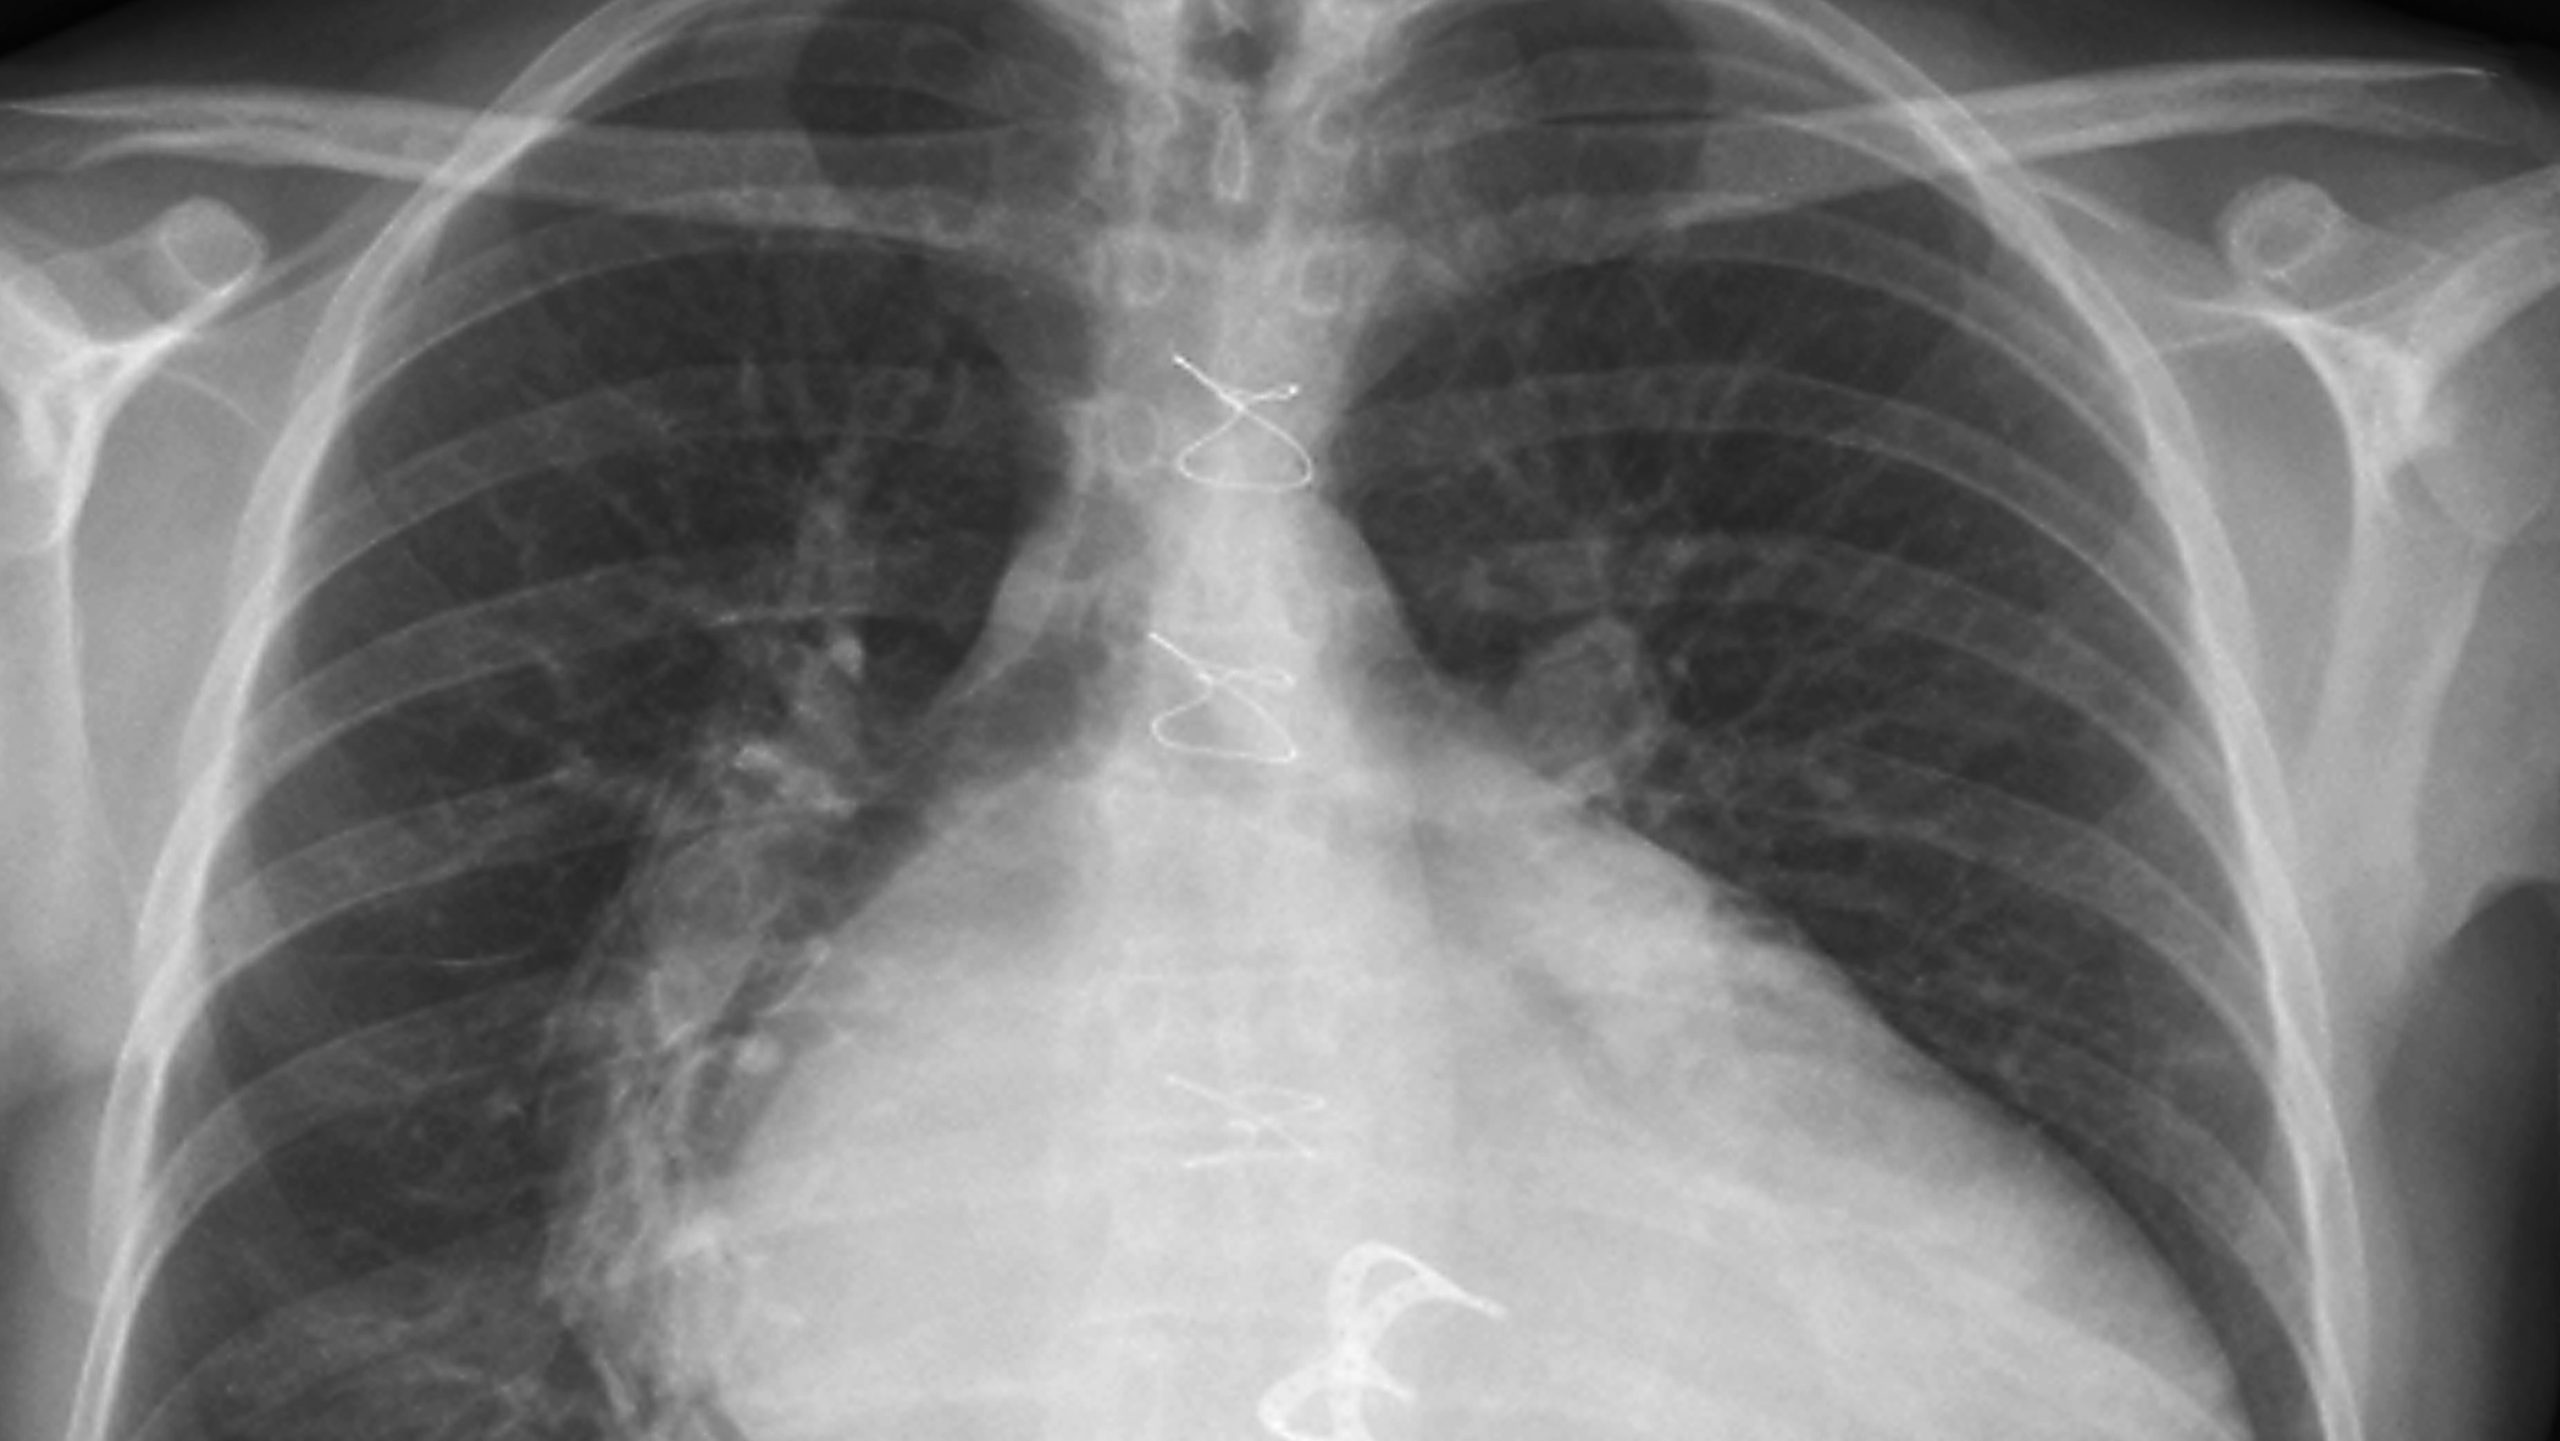

La Justicia falló a favor de un ciudadano de la provincia de La Pampa que demandó a una compañía de seguros por mala praxis. El hecho que desencadenó la denuncia fue una operación ante la sospecha de un tumor, el cual en realidad eran una gasas que salieron en las últimas radiografías. Estas fueron dejadas por médicos en su interior durante una cirugía de válvula del corazón.

El objeto en su interior, de más de 30 centímetros, fue suficiente para que la Cámara de Apelaciones Civil, Comercial, Laboral y de Minería de Santa Rosa fallara a su favor. De esta manera, admitió de manera parcial la demanda contra los cirujanos.

Hace más de dos años, el demandante debió ser sometido a una operación de válvula de corazón. Al detectarse el supuesto tumor, o quiste hidatídico, en otro establecimiento médico, tomaron la decisión de llevar a cabo una nueva cirugía. Sin embargo, al momento de llegar a la zona en cuestión, se toparon con, lo que la ley denominó, un “oblito olvidado”.